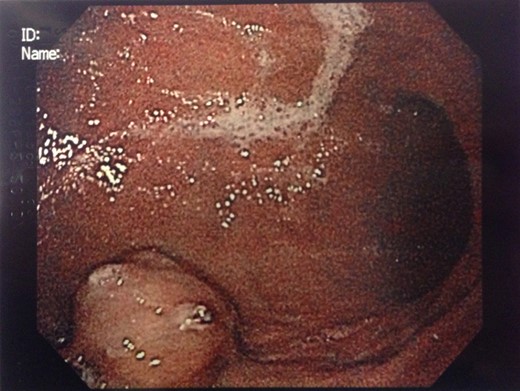

Endoscopic findings of gastric GTs are that of a submucosal mass, typically in the antrum or distal body, with either normal mucosa or ulceration [3, 4] (Fig. 1). CT shows a well-defined submucosal tumor with a clear margin, strong enhancement in the arterial phase, and prolonged enhancement in the delayed phase [4, 5] (Fig. 2). Often confused with GIST, the distinguishing features are that the density of GISTs is lower than that of GTs, and GISTs do not exhibit prolonged enhancement in the delayed phase [5]. On EUS, the GT is found in the fourth endosonographic layer, with a heterogeneous appearance. In one small study of seven gastric GTs, six demonstrated the characteristic ‘peripheral halo’ sign around the tumor [5].